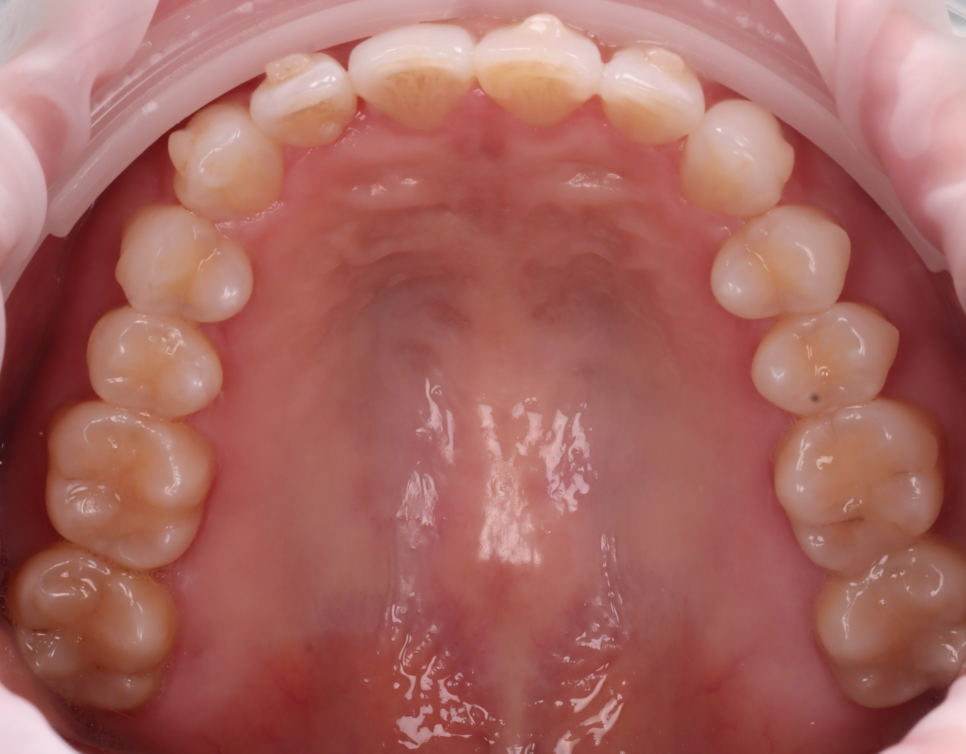

투명 교정 시에는

'어태치먼트(Attachments-부착물)'

라는 것을 붙여서 치아를 움직이는데요.

치료 계획

#11,21 길이 연장

#12 블랙 트라이앵글 메우기

#12,22 반점치 제거

이렇게 계획을 세웠습니다.